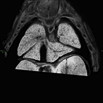

Caption Play MovieSerial 2D EFIC image stack of 2739-005-1 (E15.5) in the coronal section reveals DORV {S,D,D}, AVSD, ventricular non-compaction, cushion-like atrioventricular valve and semilunar valves

Copyright This image is from the Laboratory of Dr. Cecilia Lo, a member of the Cardiovascular Development Consortium (CvDC), Bench to Bassinet (B2B) program of the National Heart Lung and Blood Institute (NHLBI), and is displayed with the permission of the authors. J:175213

b2b2739Clo Mutant line 2739; Bench to Bassinet Program (B2B/CVDC), mutation 2739 Cecilia Lo

b2b2739Clo/b2b2739Clo C57BL/6J-b2b2739Clo